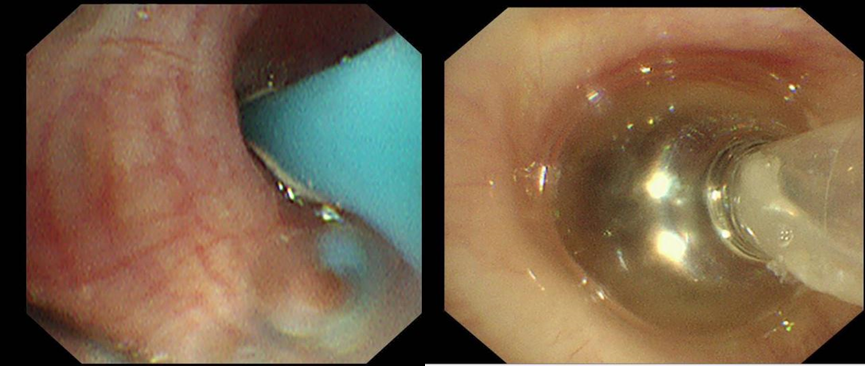

首次检查中,团队运用Chartis测压技术,对右上叶、右中间支气管进行测压,判断漏气位于右上叶。再对右上叶后段、前段、尖段测压后,见右上叶尖段漏气,随着负压加大,吸气压曲线明显,反复测试多次见右上叶尖段漏气减少明显,考虑持续漏气的部位是右上叶尖段。同时,于右上叶尖段予球囊扩张导管进一步堵塞,胸腔负压引流瓶未见明显气泡漏出,进一步证实右上叶尖段漏气。Chartis测压技术如同给气道做“精准导航”,成功定位右上叶尖段为漏气部位。这一关键发现,为后续治疗奠定基础,明确了“补漏”的目标靶区。

基于首次检查结果,医疗团队针对目标靶区精准实施支气管镜治疗。通过冷冻技术处理瘘口局部组织,促进组织修复反应,同时填塞可吸收明胶海绵。明胶海绵迅速填充瘘口,物理阻断气体泄漏,手术过程中患者未见明显漏气。然而,一周后患者再次出现漏气症状,提示单纯冷冻与明胶海绵填塞未能彻底解决问题,治疗需进一步升级。